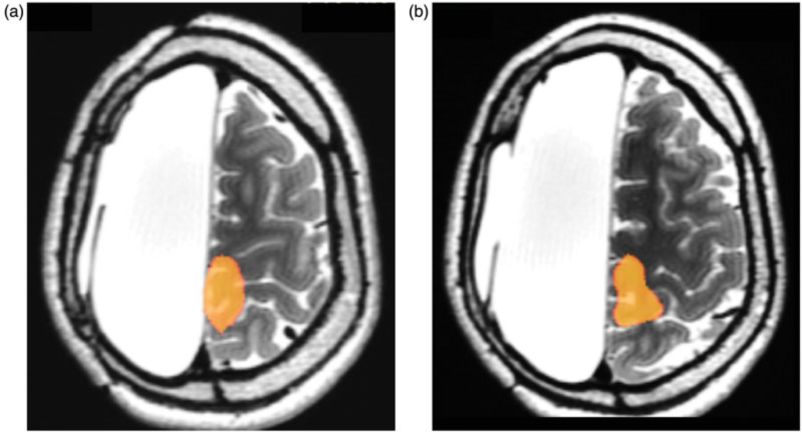

患者女性,五岁半时出现左侧局灶性癫痫发作。药物治疗一年,继发左侧轻偏瘫;颅脑MRI成像显示,右侧大脑半球缺失,诊断为Rasmussen脑炎(图1)。20个月后,七岁时发展为重度偏瘫和癫痫持续状态,药物治疗无效果。患儿语言功能好,学业达同龄人水平。给予施行右侧大脑半球全切除术。术后无并发症,恢复良好,癫痫发作缓解。

图1. 术前MRI扫描显示,右侧大脑半球缺失,残留右侧下丘脑、萎缩的右侧大脑脚和右侧脑干。左侧大脑半球结构正常。